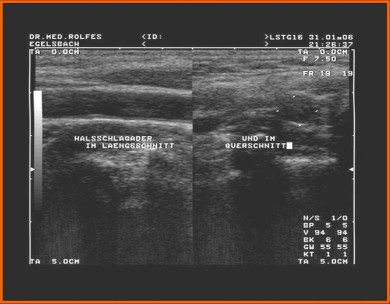

Im Bereich der Ultraschalldiagnostik bieten wir in unserer Praxis neben den Standarduntersuchungen ein Gefäßscreening an. Dabei können Verengungen (Stenosen, Plaquebildungen) in wichtigen Gefäßen (z.B. der Halsschlagader, A. carotis) lokalisiert werden.